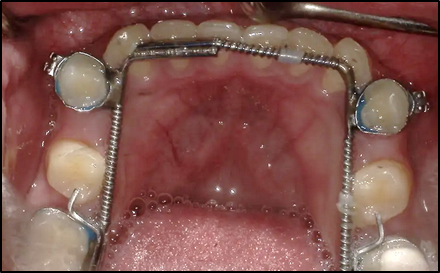

Image 2. Expansion of the 1st and 2nd bicuspid region achieved without flaring the lower incisors (Fig 6)

Expansion is most stable in descending order : 1st molar 2nd bicuspid, 1st bicuspid, canine and  last incisors!  Notice arch size is increased but minimal expansion in the cuspijd and incisor area.